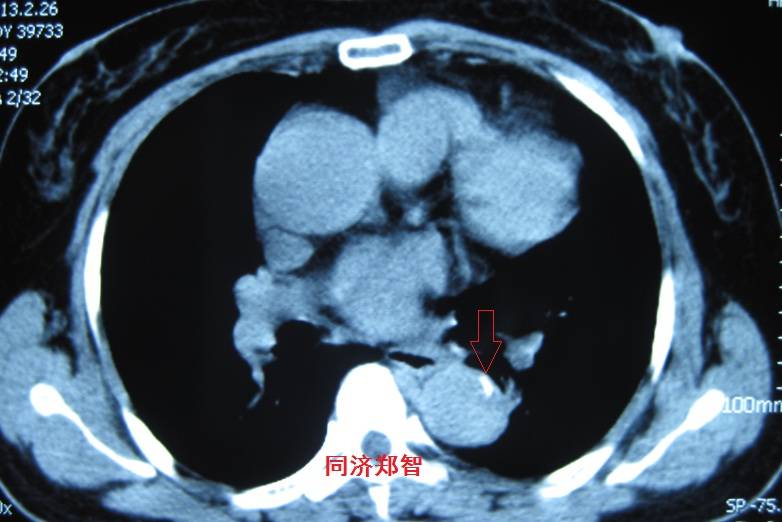

病例十

腹主动脉平扫CT提示正常外周一圈的钙化影中有内移的钙化影(红色箭头所示),CTA 证实为腹主动脉夹层